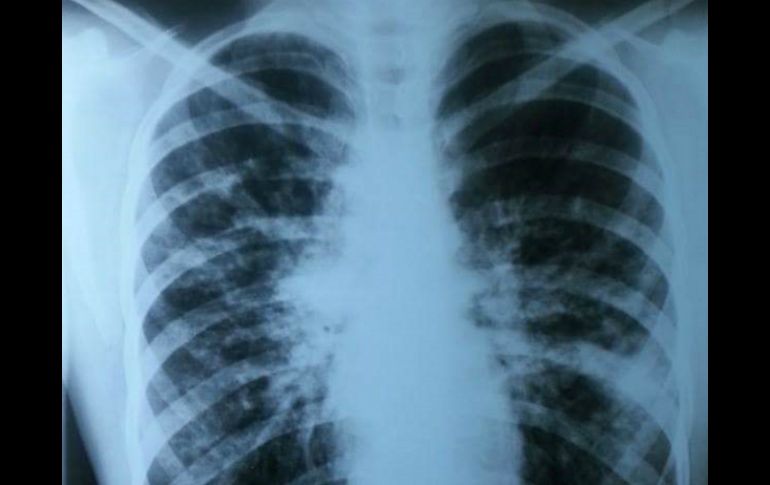

Tecnología | Algunos de los síntomas son tos crónica, falta de aite, sinusitis y deshidratación Detección temprana de fibrosis quística mejora expectativa de vida Algunos de los síntomas son tos crónica, falta de aite, sinusitis y deshidratación Por: NTX 26 de marzo de 2016 - 18:40 hs La detección oportuna es lo que marca la diferencia en la calidad y expectativa de vida de un paciente. NTX / ARCHIVO CIUDAD DE MÉXICO (26/MAR/2016).- Tos crónica, falta de aire al realizar actividad física, sinusitis y deshidratación, son algunos de los síntomas que indican la presencia de fibrosis quística (FQ) en los niños. La fibrosis quística es considerada como una enfermedad rara y de origen genético, para que un niño sea portador es necesario que ambos padres tengan dicha mutación genética, informó en un comunicado el Laboratorio Roche. Así, explicó en un comunicado, si ambos padres poseen dicha mutación, al concebir un hijo tendrán 25 por ciento de probabilidades de que el niño tenga FQ, 50 por ciento de que éste sea un portador (sano) y 25 por ciento de no esté enfermo ni sea portador. La compañía con sede central en Basilea, Suiza, indicó que en México cada día nace al menos un niño con FQ y se estima que al año, son 400 los infantes diagnosticados con este padecimiento. "En México se estima que existen poco más de 1.5 millones de portadores sanos de la enfermedad, es decir, que al menos una de cada 60 personas es portadora de la mutación genética causante de este padecimiento", señaló la neumóloga pediatra, Claudia Garrido. La especialista adscrita al Servicio de Neumología Pediátrica del Instituto Nacional de Enfermedades Respiratorias (INER), añadió que lo lamentable de la situación es que como no se presenta ningún síntoma los padres no se dan cuenta. Ante esta situación, explicó la especialista, la detección oportuna de esta enfermedad es lo que marca la diferencia en la calidad y expectativa de vida de un paciente. En ese sentido, expuso que "es importante estar atento a otro tipo de síntomas como dolor abdominal por estreñimiento grave, aumento de gases o abdomen que parece distendido, náuseas o falta de apetito, heces pálidas, fétidas y con moco, y pérdida de peso". Así, subrayó la importancia de detectar con tiempo dicho padecimiento, de lo contrario, la expectativa de un niño con fibrosis quística es de cuatro años de edad. Garrido explicó que con un diagnostico temprano, así como mejores formas de tratamiento, cada vez son más los pacientes en México que alcanzan la vida adulta plena y productiva. Al respecto, señaló que "es necesario ampliar los recursos y mejorar la infraestructura actual, para que nuestros pacientes alcancen una esperanza de vida promedio mayor a los 40 años". A su vez, explicó que una de las formas efectivas para detectar la FQ es mediante la prueba del tamiz neonatal. Así, refirió que "el mejor momento para realizar el diagnóstico es antes de la aparición de síntomas y complicaciones, y esto puede lograrse a partir del tercer día después del nacimiento". La especialista explicó que una de las ventajas del tamiz neonatal es que permite identificar enfermedades raras pero serias en el recién nacido antes de que se manifiesten sus síntomas. En caso de resultar positivo a la prueba de fibrosis quística, es necesario realizar un estudio confirmatorio conocido como "la prueba del sudor", en la que se toman en cuenta las cantidades más altas de sodio y cloro en el sudor. Temas Ciencia médica Enfermedades Calor de hogar Salud general Lee También Inapam: Así puedes acceder a consultas médicas GRATIS con la credencial INAPAM: ¿Cómo solicitar un turno para consulta médica gratuita? Sheinbaum defiende el impuesto a bebidas azucaradas ¿Cuál es el ejercicio que quema más calorías? Recibe las últimas noticias en tu e-mail Todo lo que necesitas saber para comenzar tu día Registrarse implica aceptar los Términos y Condiciones